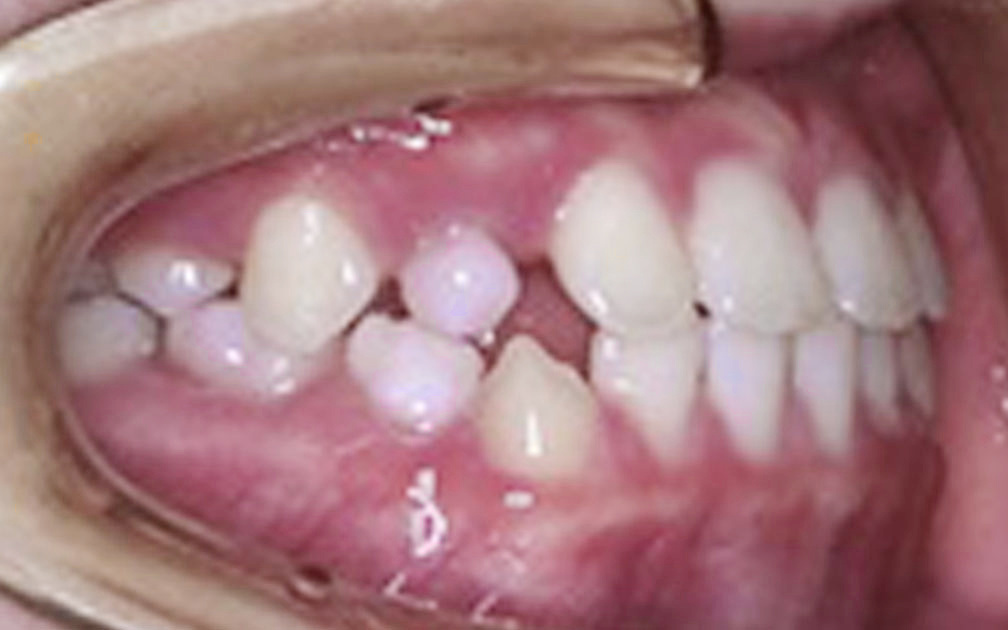

矯正の症例4 (診断名)開咬(カイコウ)

(患者様の主訴)前歯で噛めない

(治療開始年齢)15歳9カ月

(主な治療装置)エッジワイズアプライアンス

(抜歯部位)上下第1小臼歯4本抜歯

(治療期間)2年5カ月

(治療費)¥860000

(個別リスク・副作用)当初より前歯部歯根が短く、前歯部の挺出が必要な症例なので、さらに歯根が短くなるリスクがある。

舌の突出の影響が大きいため、矯正治療後も舌癖により後戻りが起こるリスクがある。長期にわたる舌癖のコントロールが必要となる